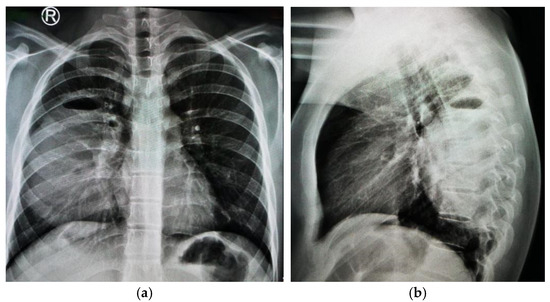

1.9.1. Case 1

1.9.2. Case 2